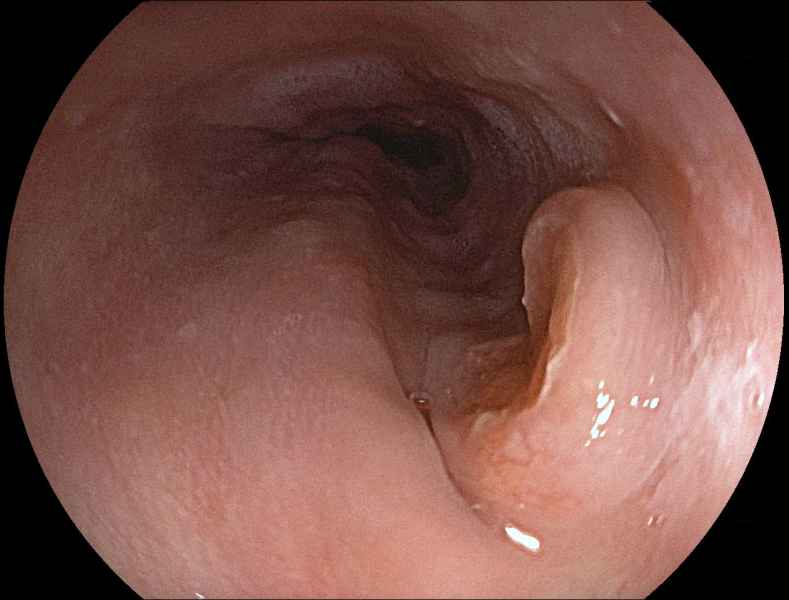

An uncommon diagnosis done by colonoscopy

Fotografia

Colocolic intussusception

Fotografia